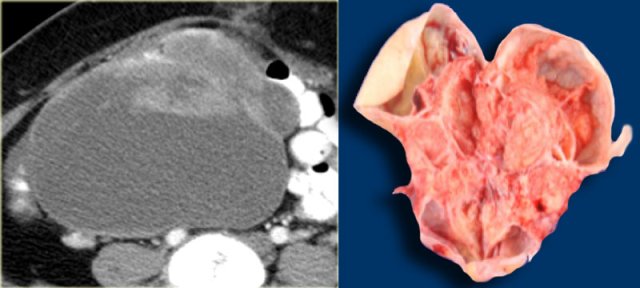

Mature cystic teratoma

A very common benign ovarian lesion that may appear cystic is a mature cystic teratoma, also called dermoid cyst.

Mature in this context means benign, as opposed to the immature, malignant teratoma.

Benign cystic teratomas typically occur in young women of child-bearing age.

At imaging they are usually unilocular (up to 90%) but can be multilocular, and are bilateral in ~15%.

Up to 60% may contain calcifications.

The cystic component is fluid fat, produced by sebaceous glands in cyst lining.

The presence of fat is diagnostic.

Axial T1-weighted image in the same patient shows a bright lesion with an internal septation.

A septation is seen in about 10% of thse lesions.

On the T1-weighted image with fat suppression there is suppression of the signal.

This confirms the fatty content and is diagnostic of a teratoma.

Classic low attenuation consistent with fat in a right sided cystic teratoma at CT.